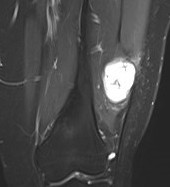

Saphenous nerve schwannoma

Schwannoma on tibialis posterior nervee